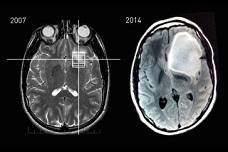

Curiosity staves off cancer, saves life

Steven Keating’s cerebral approach to his brain scans leads to discovery of baseball-sized tumor and makes him an advocate of open-source health data